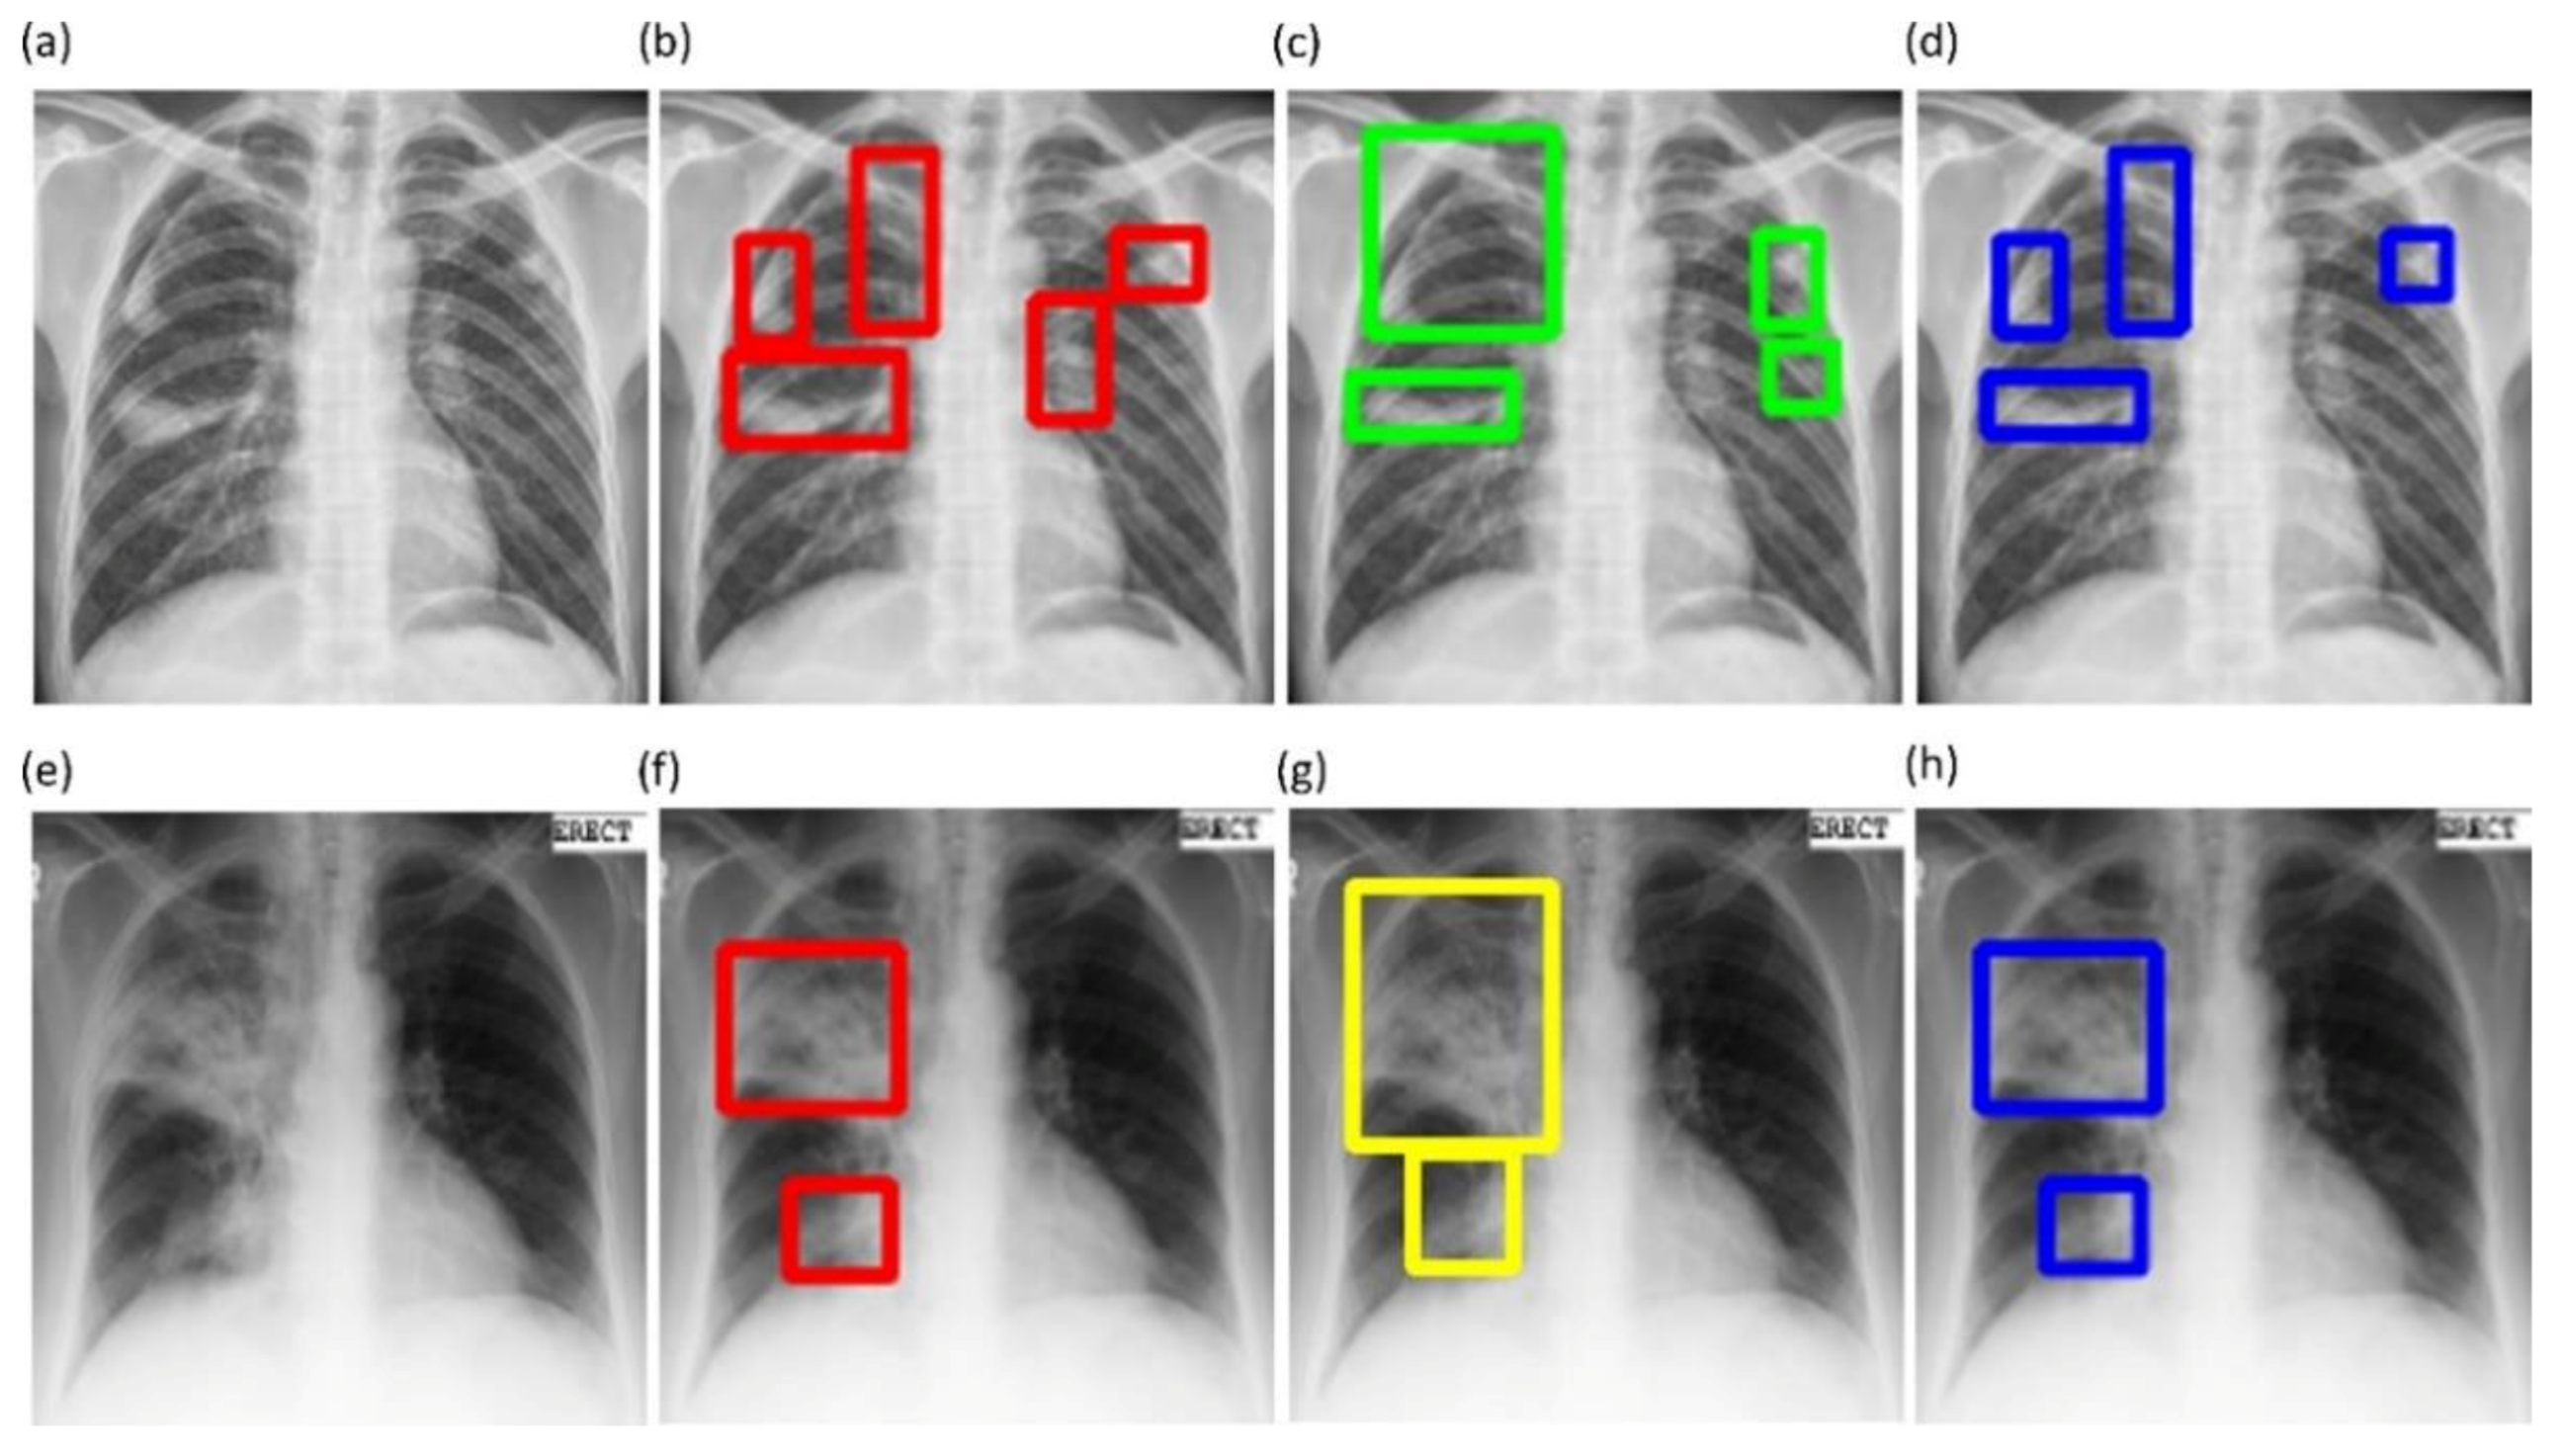

Figure 6 shows instances of TB-consistent

ROI annotations made by the radiologists and the STAPLE-generated consensus

ROI for a sample CXR instance from the Shenzhen TB CXR-Subset-2 and Montgomery TB CXR collections respectively.

The GT disease annotations for Shenzhen TB CXR-Subset-2 are set by verification from two expert radiologists, hereafter referred to as R1 and R2. The GT annotations for the Montgomery TB CXR collection are set by the verification from two expert radiologists, hereafter referred to as R2 and R3. The expert R2 participated in both annotations. The collective experience of the experts counts to 65 years. The web-based VGG Image Annotator tool [

41] is used by radiologists to independently annotate these collections. The radiologists are asked to draw rectangular bounding boxes over the regions that they believed to show TB-consistent manifestations. We chose to use bounding boxes rather than fine segmentation to maintain similarity to the TBX11K data recognizing that there will be noisy pixels due to the bounding box and the variability from multiple expert annotators. The annotations are performed in independent sessions when the radiologists annotated the TB-consistent ROI in these CXR images. The annotations from individual radiologists are later exported to a JSON file for subsequent analyses. The experts’ annotations would be made publicly available upon acceptance.